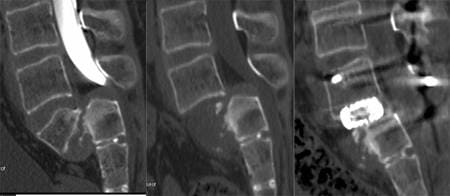

Obelisc – импланты для замещения дефектов грудных и поясничных позвонков при травмах, опухолях, инфекционных и дегенеративных процессах.

Перелом тела L2.

Передний спондилодез L1-L3 с замещением тела L2 имплантом Obelisc.